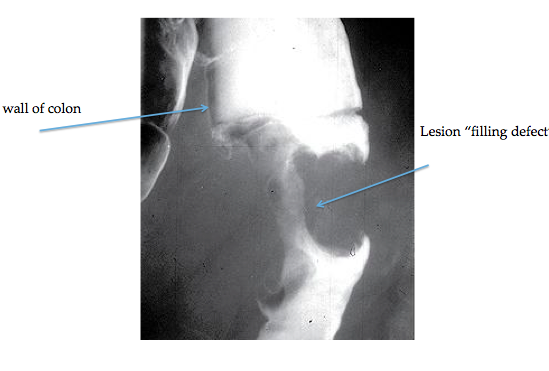

Barium enema

“apple-core” lesions

you have to prep yourself. Then they inject barium through the rectum which coats the colon. Look for things called apple core lesions.